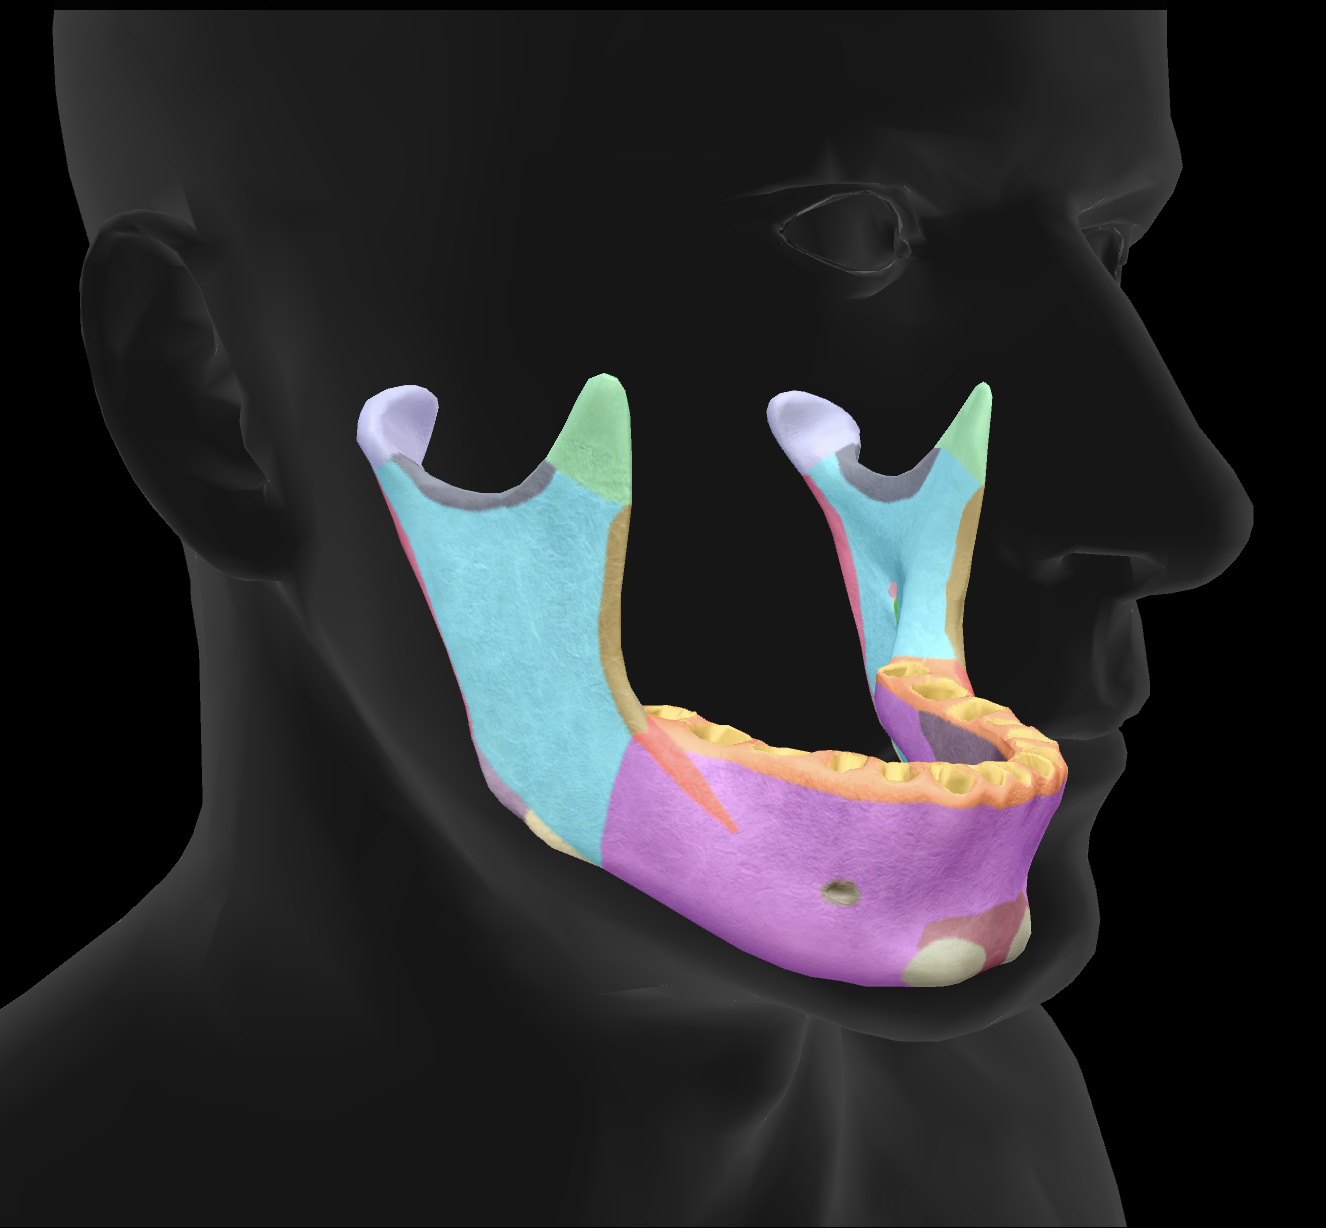

What is the name of this feature?

mandibular condyles

What is the name of this feature?

ramus

What is the name of this feature?

alveolar process

What is the name of this feature?

mandibular notch

What is the name of this feature?

angle

What is the name of this feature?

body

What is the name of this feature?

coronoid process